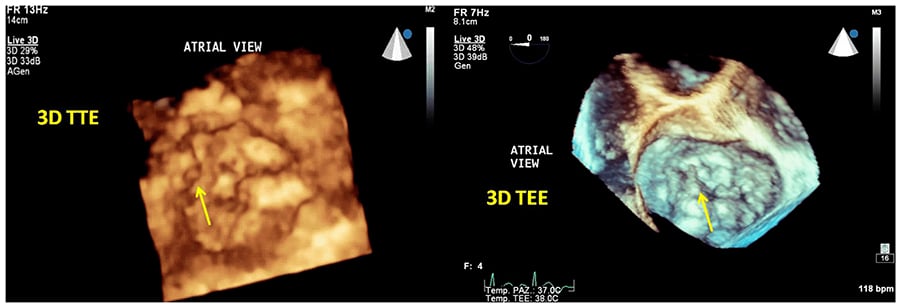

اکوکاردیوگرافی سهبعدی (Three-dimensional echocardiography)

اکوکاردیوگرافی سهبعدی از اکوکاردیوگرافی مری یا ترانستوراسیک برای ایجاد یک تصویر سهبعدی از قلب شما استفاده میکند که شامل چندین تصویر از زوایای مختلف است. این روش عکسبرداری، اغلب قبل از جراحی دریچه قلب و همچنین برای تشخیص مشکلات قلبی در کودکان تجویز میشود.

گاهی ممکن است پزشک از تزریق ماده کنتراست استفاده کند تا تصاویر واضحتری به دست آورد.